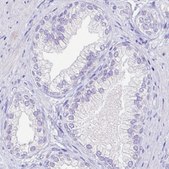

immunohistochemistry: 1:2500- 1:5000

The Human Protein Atlas project can be subdivided into three efforts: Human Tissue Atlas, Cancer Atlas, and Human Cell Atlas. The antibodies that have been generated in support of the Tissue and Cancer Atlas projects have been tested by immunohistochemistry against hundreds of normal and disease tissues and through the recent efforts of the Human Cell Atlas project, many have been characterized by immunofluorescence to map the human proteome not only at the tissue level but now at the subcellular level. These images and the collection of this vast data set can be viewed on the Human Protein Atlas (HPA) site by clicking on the Image Gallery link. We also provide Prestige Antibodies® protocols and other useful information.